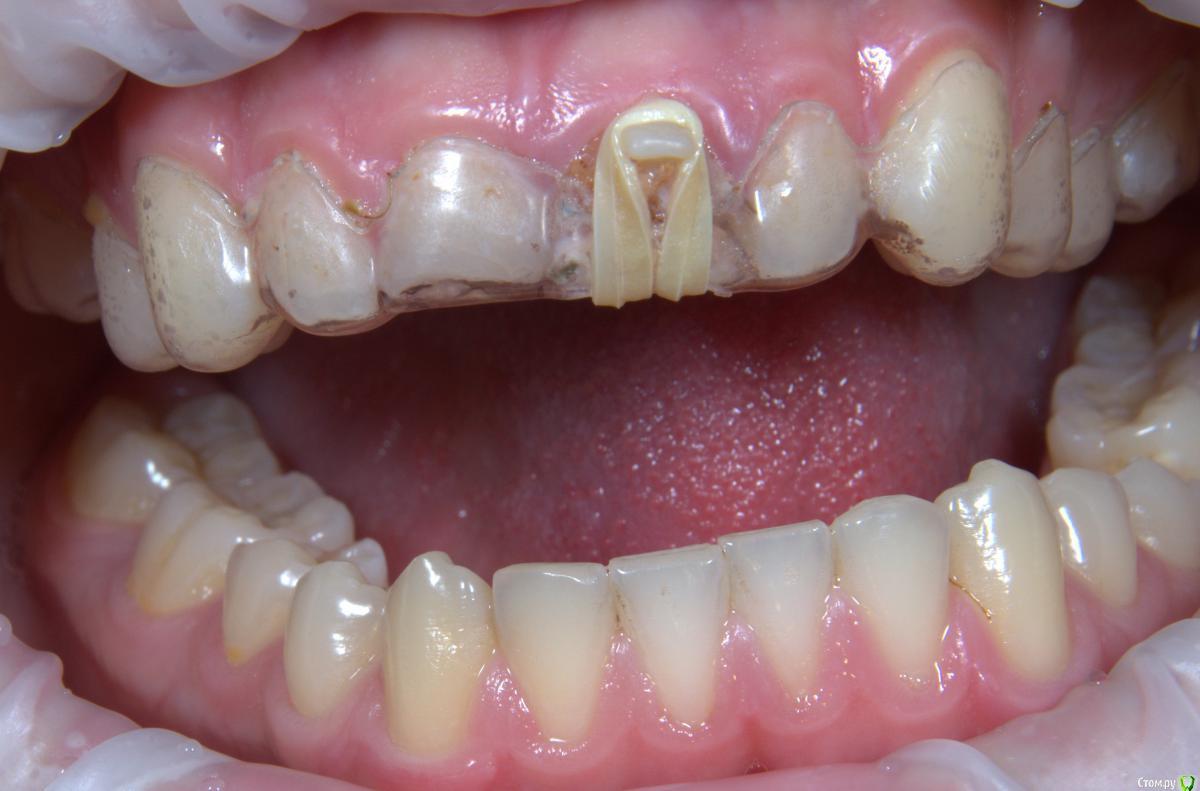

Хью Крейн Опубликовано 11 августа, 2017 Поделиться Опубликовано 11 августа, 2017 Композит на небной поверхности не мешает окклюзии? Ссылка на комментарий

kamranchick Опубликовано 11 августа, 2017 Автор Поделиться Опубликовано 11 августа, 2017 Композит на небной поверхности не мешает окклюзии?мешает, а как быть?) Ссылка на комментарий

Art 7 Опубликовано 11 августа, 2017 Поделиться Опубликовано 11 августа, 2017 ставишь стекловолоконную балку между апроксимальных поверхностях соседних зубов) Ссылка на комментарий

kamranchick Опубликовано 11 августа, 2017 Автор Поделиться Опубликовано 11 августа, 2017 ставишь стекловолоконную балку между апроксимальных поверхностях соседних зубов)Спасибо Артурчик)Попробуем так))) просто шатается сильно, страшно трогать пока что) Ссылка на комментарий

1586Doc Опубликовано 11 августа, 2017 Поделиться Опубликовано 11 августа, 2017 (изменено) Это обычная силиконовая каппа ?вытягиваем, потом стабилизация ? Как на долго? Изменено 11 августа, 2017 пользователем 1586Doc Ссылка на комментарий

kamranchick Опубликовано 11 августа, 2017 Автор Поделиться Опубликовано 11 августа, 2017 Это обычная силиконовая каппа ?вытягиваем, потом стабилизация ? Как на долго?капу сделали вакуум формером, помоему она пластмассовая вроде. стабилизация 2-3 месяца... Ссылка на комментарий